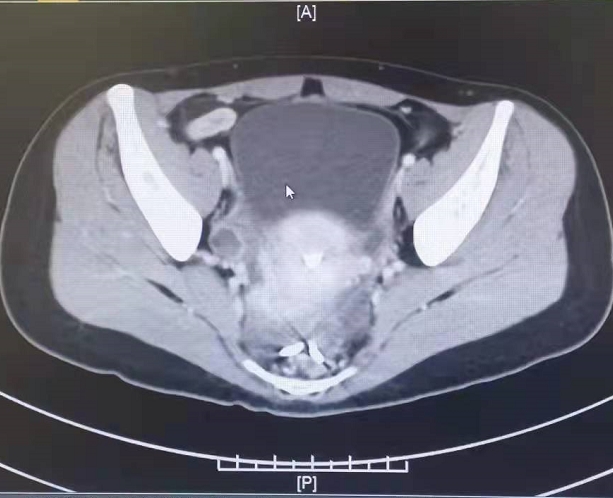

来到重医附二院胃肠肛肠外科后,王亚旭、顾海涛教授考虑到患者病情特殊性,再次为张女士完善了腹部CT检查,检查见节育环主体已移位至直肠子宫陷凹,部分突入了直肠腔,且本次检查偶然发现,张女士的阑尾明显增粗,合并有囊性病灶,局部肠壁增厚,考虑粘液腺肿瘤可能性大。顾海涛教授考虑,该患者合并有直肠异物及阑尾肿瘤两个问题,如何更好地为患者同时解决两个问题成为他考虑的核心内容,于是胃肠肛肠外科联合妇科、放射科开展多学科诊疗,共同展开了术前讨论,设想术中可能出现的种种情况,制定了多种手术方案。与患方沟通后,最终选择了兼顾直肠异物和阑尾肿瘤,且创伤最小的治疗方案:即行经肛直肠异物取出+腹腔镜探查术。

张女士腹部CT图像(可见直肠异物、阑尾肿瘤)